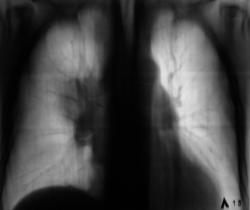

После взятия поциента "на контроль" произведи стандартное дообследование. Пациент жалоб не предъявляет, обращает внимание на небольшую одышку и "сухой" непродуктивный кашель. Произведено стандартное дообследование.

деформация правого корня. Он смещён немного вверх. Картина похоже на течение онкопроцесса.

Новообразование в области правого верхнедолевого бронха, центральная форма, ателектаз или обструктивный пневмонит в третьем сегменте, лимфангит во всей доле, расширение вехнего средостения вправо - метастазы?

Валентин Львович, а Вы не хотите сделать боковую томограмму через тень (корень) и томограмму на правый в/долевой бронх. Потому как ни одной из томограмм ни тень, ни бронхи справа не в срезе, а есть у меня такое впечатление, что имеет место периферический узел в S3, проекционно накладывающийся на тень корня, кроме того, при таком конгломерате в корне, должна быть более выражена гиповентиляция...